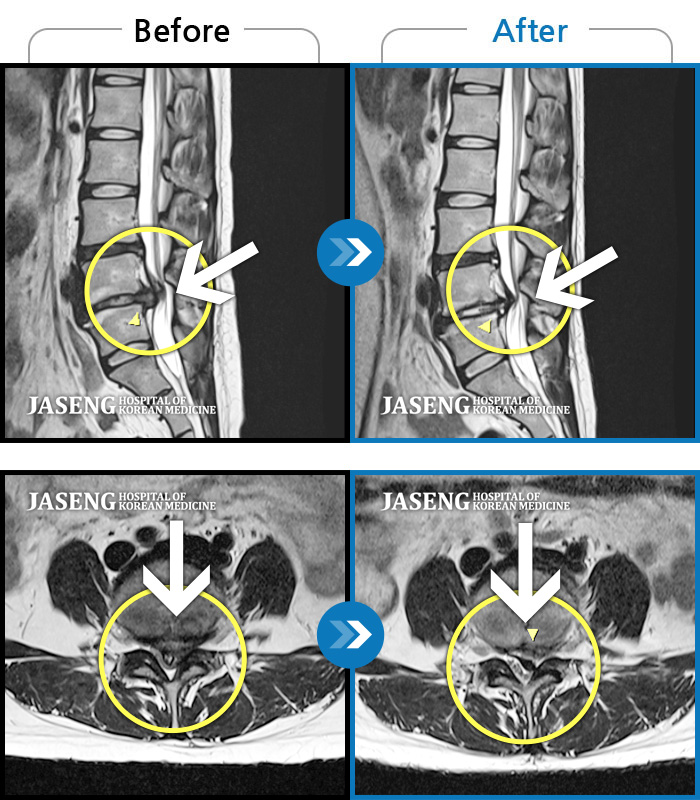

허리디스크

광주 · 김준수 원장

양측 허리 통증, 우측 다리까지 이어지는 통증과 저림, 모든 자세에서 통증 심화

촬영시기

2022.09.02 ~ 2024.08.02

2024.08.14

조회수 124